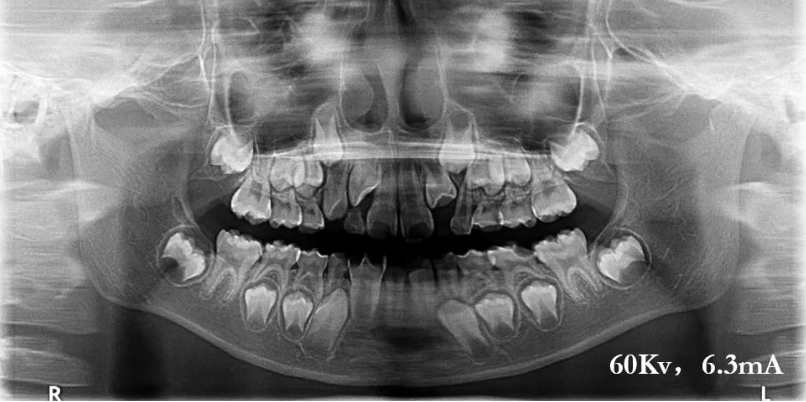

下面是位小患者,在前牙区发黑,证明X线平均能量过高,穿透力过强。

当电压从70降到60时,得到了第二张曲面断层片,上颌显影比第一张好多了。

曲面断层片怎么看口腔精读 | 一次性教你看懂曲面断层片!_https://www.jmylbn.com_新闻资讯_第18张

上颌前牙区、下颌前牙区牙位辨认

患者处于混合牙列期,可以看到右侧前牙区有多生牙,下颌有融合牙的存在。